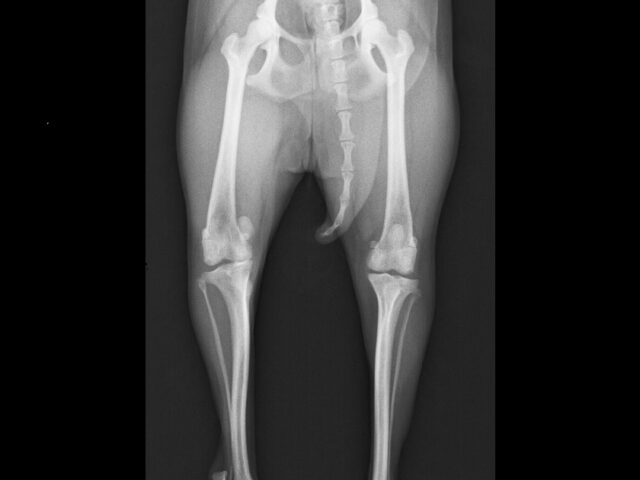

01 高度医療

動物用CTを用いた検査が可能です。経験豊かな獣医師が患者様の状況に合わせて最善の検査・治療をご提案いたします。また、軟部組織外科など難度の高い手術症例にも対応しています。